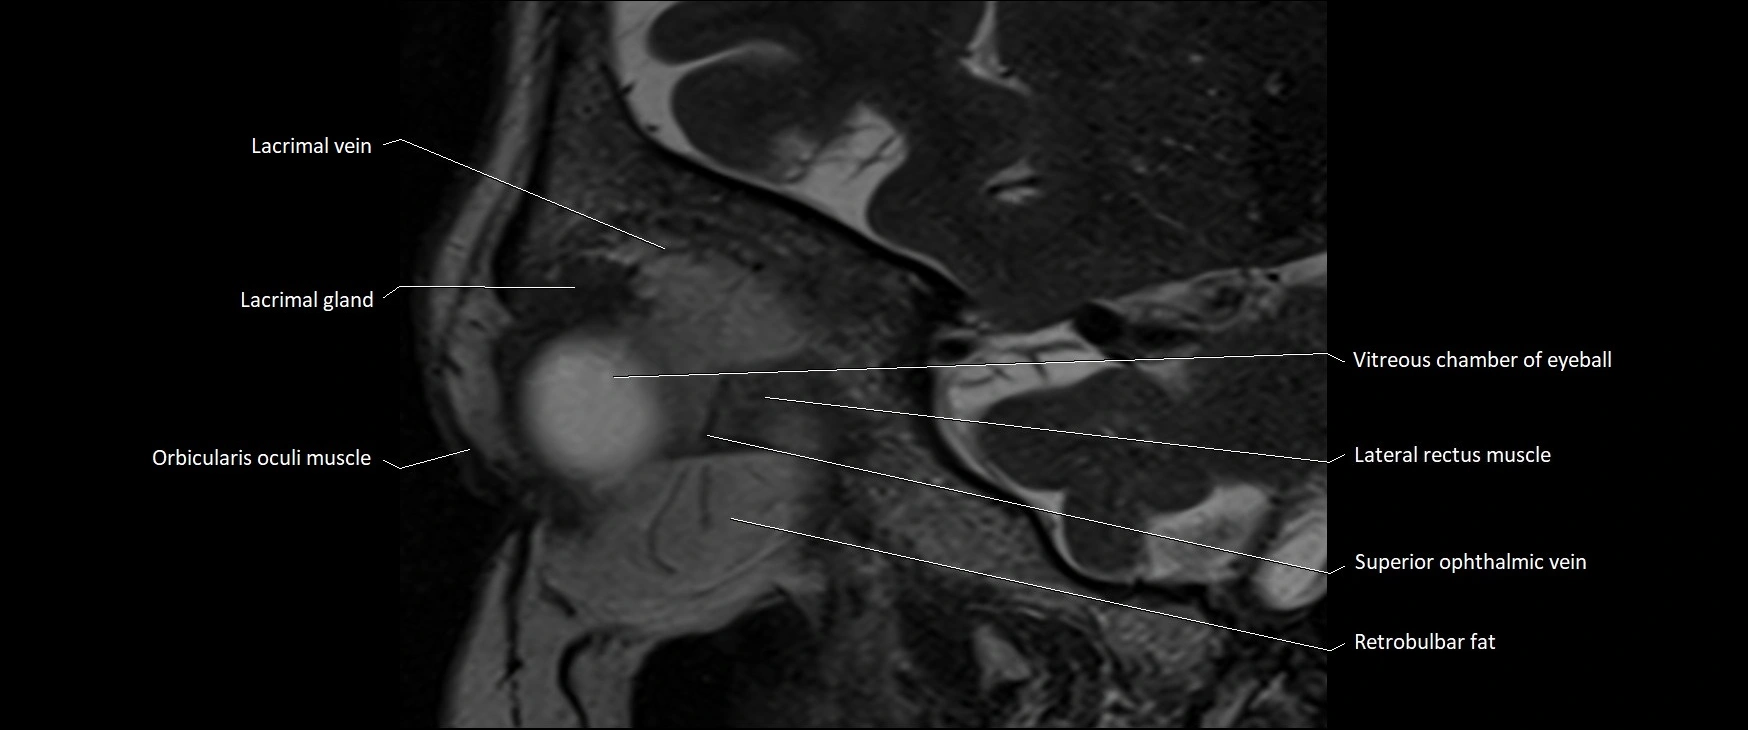

MRI images